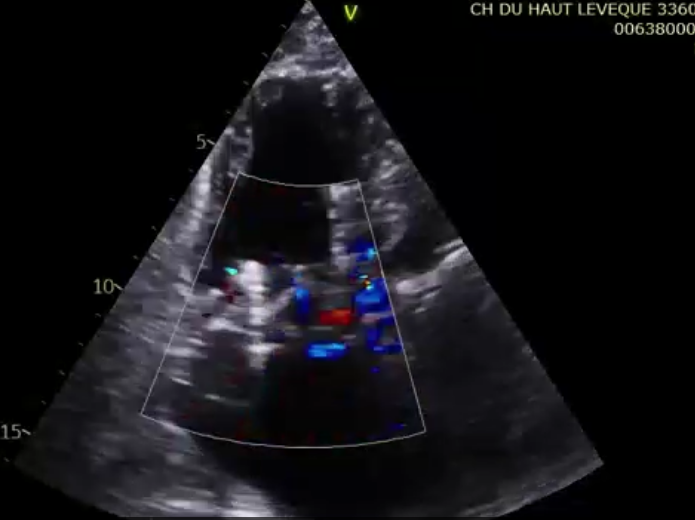

術前超聲提示大量三尖瓣反流

術后超聲提示微量瓣周漏